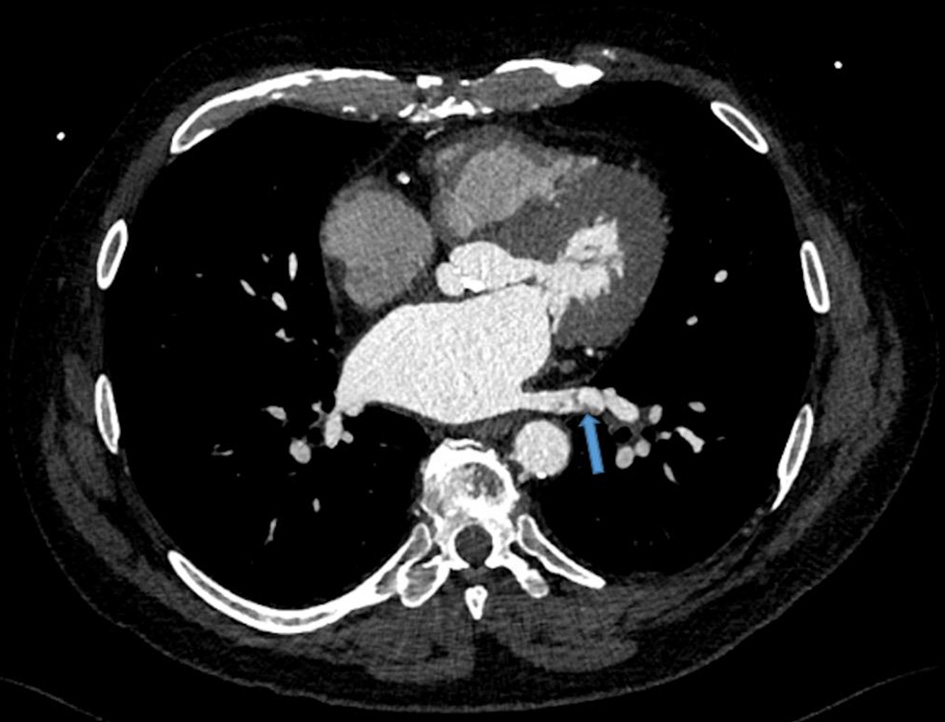

However, due to persistent neutropenia and rising liver enzymes, lenalidomide was lowered to 15 mg at cycle 5. This was further reduced to 10 mg by cycle 6 and 5 mg by cycle 10 for similar. During the 10th cycle, patient had a syncopal episode with worsening shortness of breath. Due to previously suboptimal stress test, coronary CTA was performed along with fractional flow reserve (FFR). CT-FFR showed diffuse atherosclerotic disease in left anterior descending (0.79) and left circumflex coronary artery (0.72) that did not warrant intervention. However, a thrombus in the left lower pulmonary vein was identified (Fig. 1). He was started on rivaroxaban 20 mg. Lenalidomide, dexamethasone and aspirin were discontinued. A 2-week follow-up transesophageal echocardiogram showed resolution of the pulmonary vein clot. Repeat CTA performed 2 months after initial diagnosis also confirmed clot resolution (Fig. 2). He had dramatic improvement in his dyspnea and remains off treatment for MM with plans to continue with rivaroxaban indefinitely given patient’s underlying malignancy.

![]() Click for large image | Figure 1. Left lower pulmonary vein thrombosis. Transverse view of chest via a gated 192-slice multidetector computed tomography angiogram revealed a lower pulmonary vein thrombosis (arrow). |